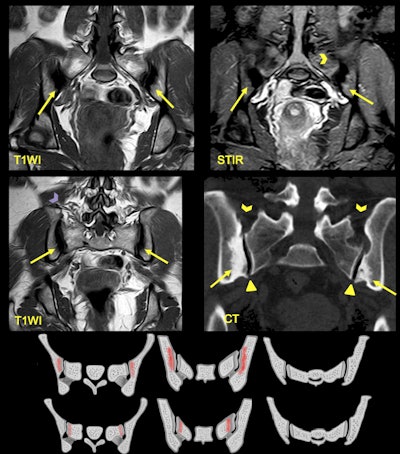

A 25-year-old woman presented with lower back pain and a history of two pregnancies. MRI shows areas of sclerosis (arrows) with low signal intensity on T1WI that arise along the iliac surface with bilateral and symmetric affection. CT shows triangular shape of the iliac bone sclerosis and lack of joint erosions. Note there is no joint space narrowing (triangle) in respect of the ligamentous compartment (arrowheads).

Cases of subchondral sclerosis in mechanical load areas of the SIJ have these features: bilateral symmetrical/bilateral asymmetrical/unilateral; iliac facet and sacral facet; higher incidence in women than men, and in the 20-60 age group; increased incidence following pregnancy; joint space and articular surface are preserved; and exceptional erosions. Remember to look for continuous BME in the cartilaginous compartment, respecting the lower third, and bear in mind it can also affect the sacral facet, the researchers emphasized.

The authors urged radiologists to suspect sacroiliitis if the following are present: asymmetrical appearance, focal involvement or intense high signals; great intensity on the iliac side; and irregular erosions with sclerosis and/or fat metaplasia.